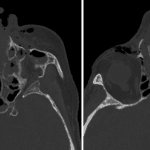

- Acute right Le Fort type I and II and left Le Fort type I, II, and III fractures with a nondisplaced left zygomatic arch fracture, fractures of the medial and inferior walls of the right orbit, fractures of all walls of the left orbit, fractures of all walls of both maxillary sinuses, fracture of the nasal septum, comminuted bilateral nasal arch fractures extending to the nasofrontal suture, and bilateral pterygoid plate fractures

- Bilateral nasoorbitoethmoid fractures with multiple bilateral ethmoid fractures in addition to the above discussed fractures

- Herniation of orbital fat through the left inferior orbital wall fracture with asymmetric rounding of the left inferior rectus muscle

- Left greater than right retrobulbar hemorrhage with left proptosis

- Fractures involving the bilateral infraorbital foramina and nasolacrimal canals

Acute right Le Fort type I and II and left Le Fort type I, II, and III fractures including a nondisplaced left zygomatic arch fracture. Additionally there are bilateral nasoorbitoethmoid fractures. Fractures notably involve the bilateral infraorbital foramina and nasolacrimal canals.

Herniation of orbital fat through the left inferior orbital wall fracture with asymmetric rounding of the left inferior rectus muscle. Recommend correlation with clinical signs of extraocular muscle entrapment.

Left greater than right retrobulbar hemorrhage with left proptosis.